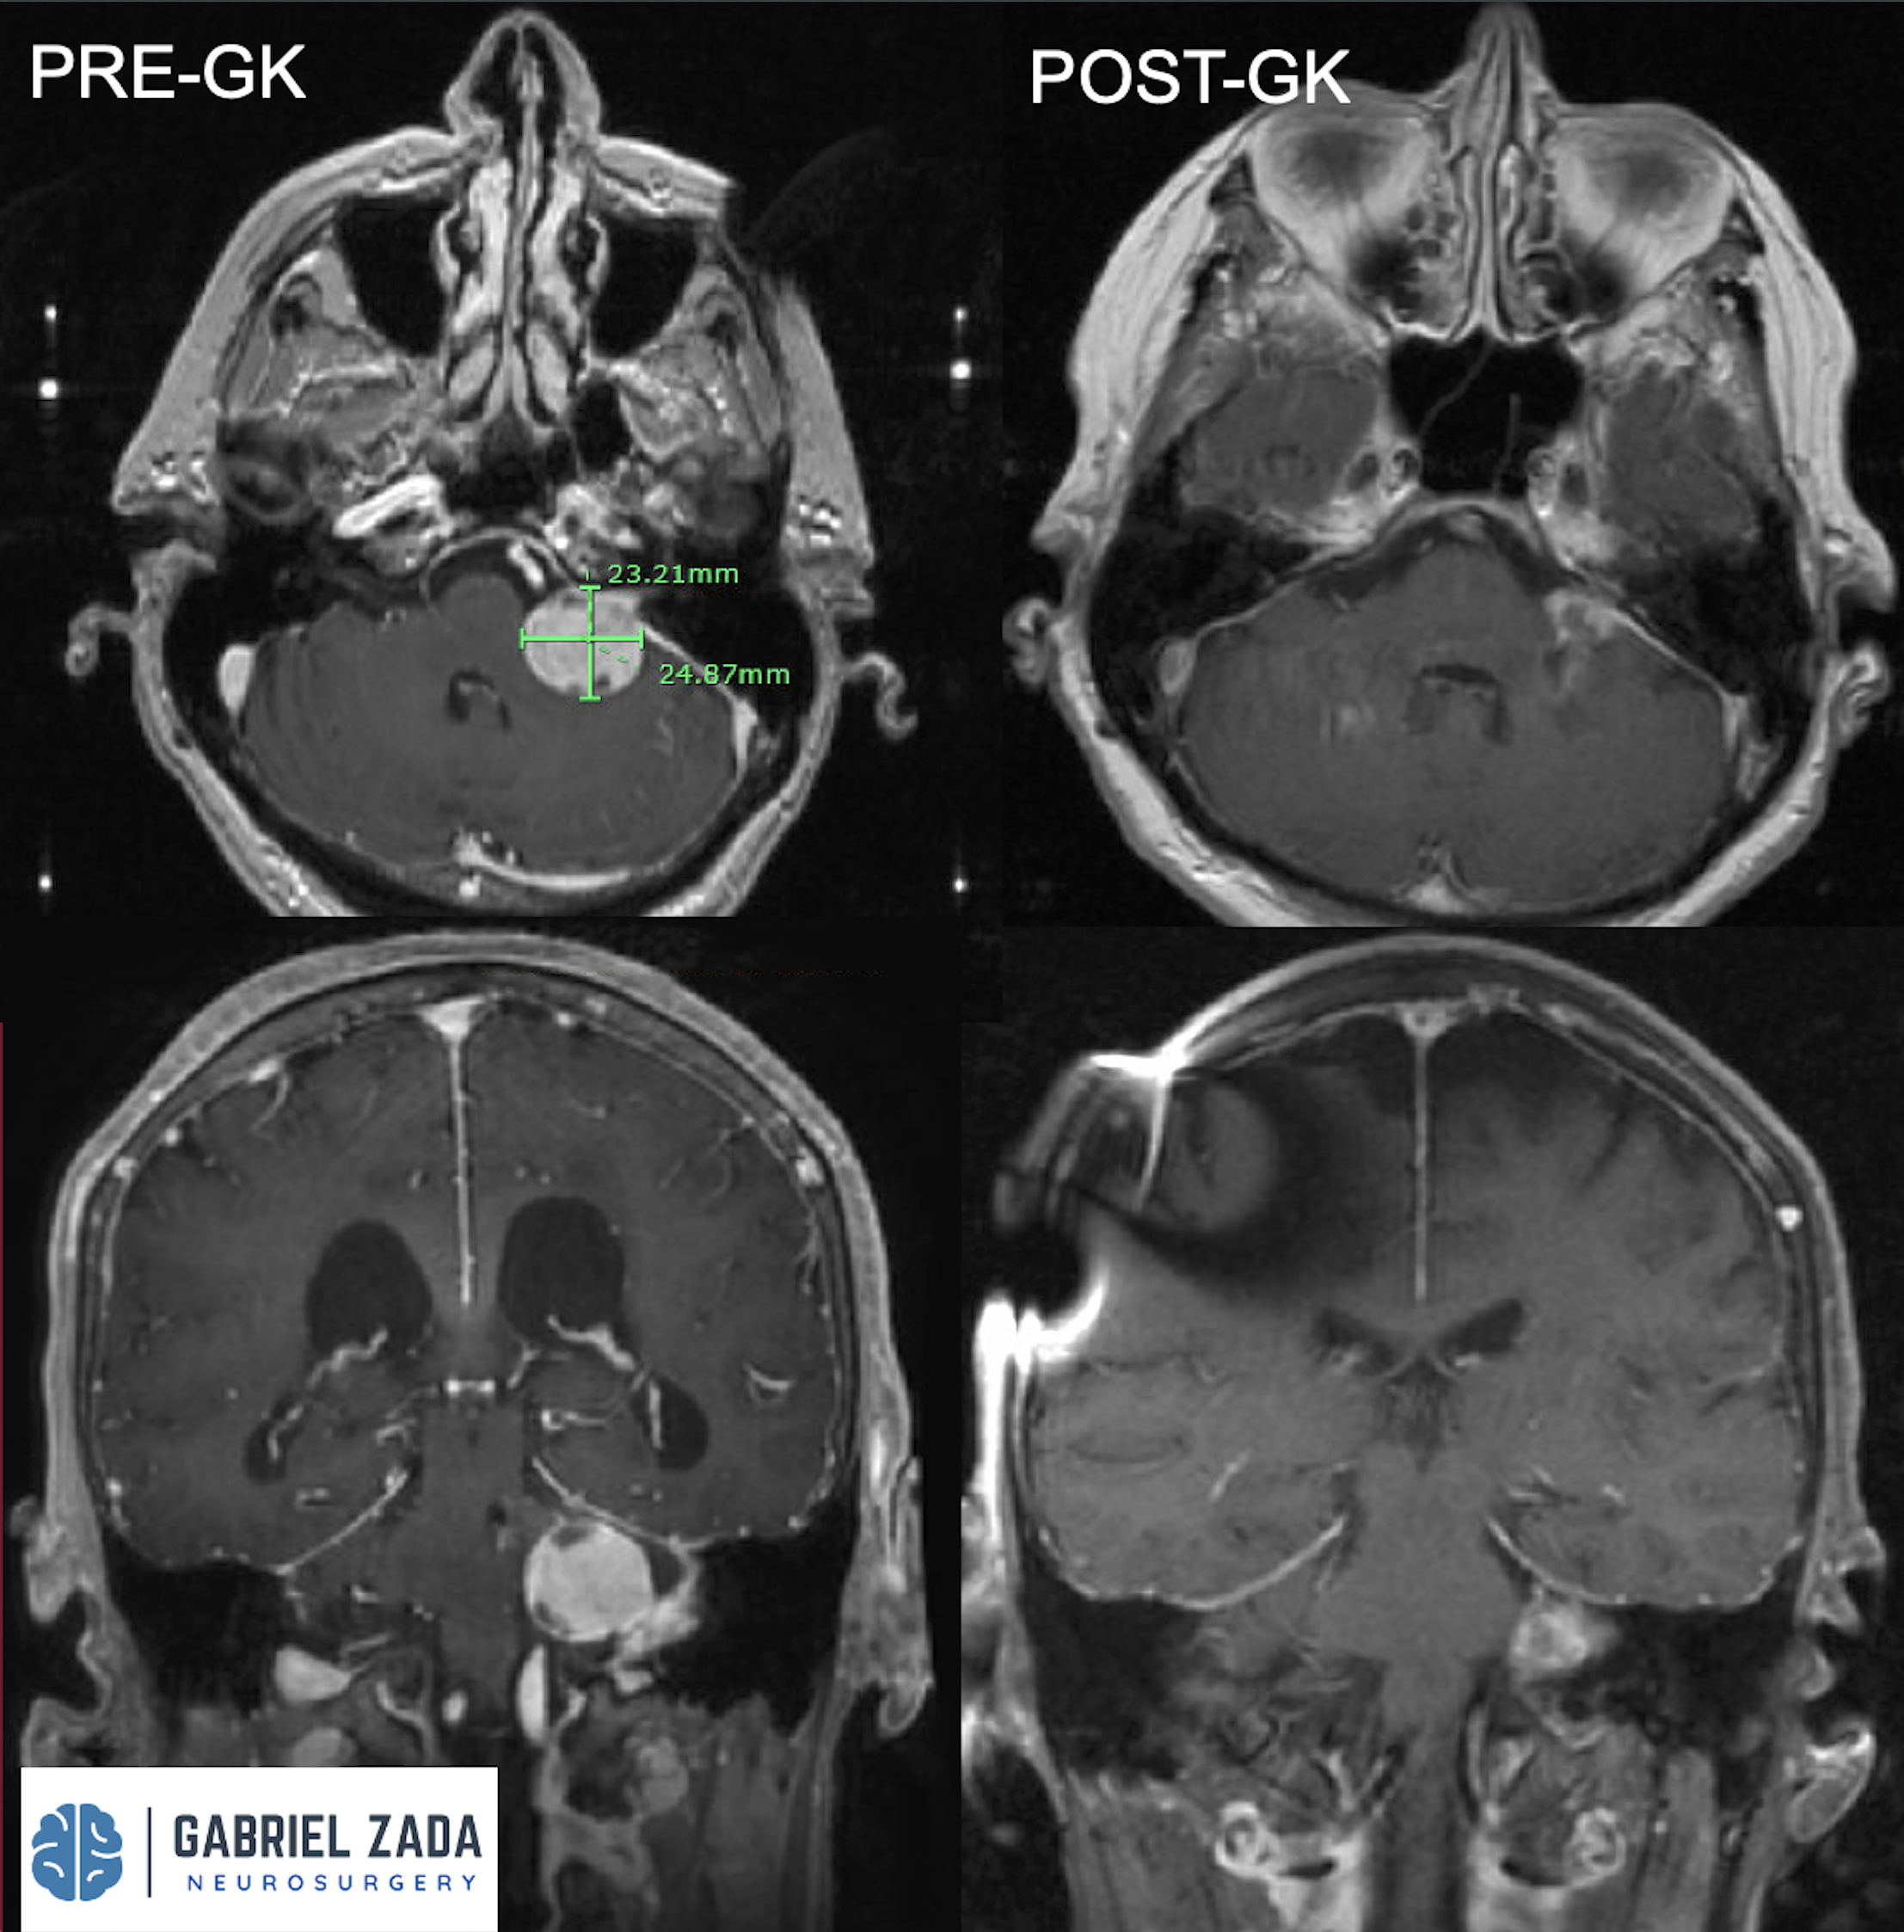

Explore this comprehensive gallery featuring pre‑ and post‑operative imaging of patients with skull‑base tumors treated by Gabriel Zada, MD, MS, FAANS, FACS. These cases highlight Dr. Zada’s expertise in advanced neurosurgical techniques and outcomes.

*Representative cases shown for educational purposes. All images de-identified. Individual results vary.